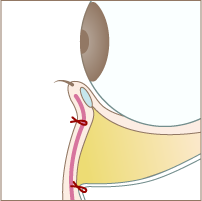

Aboutハムラ法

『ハムラ法(目の下のたるみ取り)』は、飛び出した眼窩脂肪を切除せず、ボリュームが減少した目の下のくぼみへ脂肪を移動させる治療法です。1回の施術で「眼窩脂肪の突出」「皮下脂肪の減少」を同時に解消し、目元の凹凸をフラットにすることができます。しかもヒアルロン酸などの薬剤を入れることがないので、仕上がりがナチュラルで、持続性が高いのも魅力です。

Treatment Step施術手順

Step 01

まつ毛の下の赤い点線部分を切開します。

Step 02

脂肪が溜まっている部分の下側の隔膜を切開します。

Step 03

隔膜と眼窩脂肪を一塊として引き下げ、骨膜に縫合します。

Step 04

切開した部分を縫合して完成です。